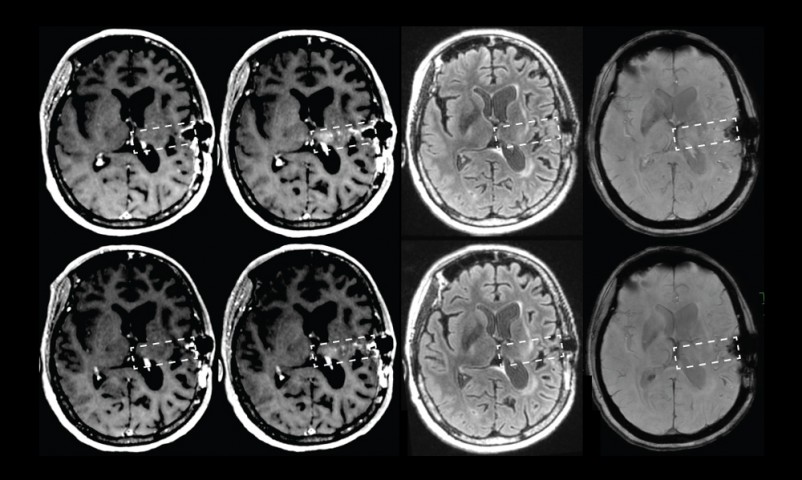

Esta máquina predice el riesgo de alzhéimer con más precisión que los médicos